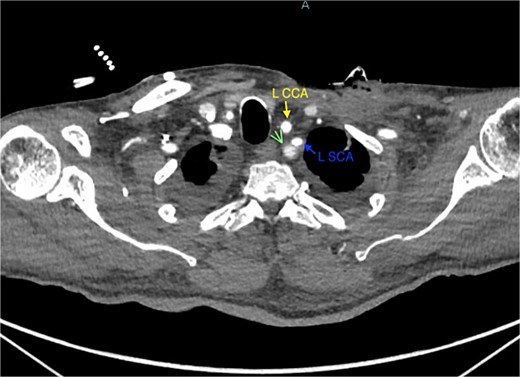

A 67-year-old male with a medical history significant for hypertension, diabetes, coronary artery disease, carotid artery stenosis, osteoarthritis, and 50 pack-year smoking history presented initially to an orthopedic surgery office for evaluation of left shoulder pain after exercising. The patient was found to have an underlying rotator cuff injury and was subsequently treated with cortisone injection. The patient subsequently developed septic arthritis, ultimately requiring incision and drainage of the abscess and resection of the sternoclavicular joint, partial first rib, and partial clavicle. The patient required multiple washouts and debridement procedures, ultimately leading to septic shock and bacteremia requiring close observation in the surgical intensive care unit. A computed tomography angiogram (CTA) of chest was performed at the time and revealed a subcentimeter penetrating ulcer, arising from the proximal left subclavian artery likely secondary to surgical trauma, which was observed nonoperatively given the patient critical status in the intensive care unit (ICU) (Figs 1 and 2). During the ICU course, the patient developed left upper extremity swelling A left upper extremity duplex ultrasound subsequently revealed a nonocclusive deep vein thrombosis of the subclavian vein and also showed resolution of a pseudoaneurysm (PSA) of the subclavian artery. The patient was started on anticoagulation at this time for a deep vein thrombosis (DVT). The patient was ultimately discharged upon resolution of his acute infection to a rehabilitation facility. During the third-month follow-up office visit, the fistulous connection between the subclavian artery and vein was found incidentally on left upper extremity duplex ultrasound (Fig. 3). Physical exam of the patient was otherwise unremarkable with palpable upper extremity pulses and the patient did not appear to have any symptoms related to the fistula including upper extremity swelling or open wounds. The patient was scheduled for an elective repair of the fistula via endovascular stent graft placement. The patient was brought to the operating room, and the radial artery was accessed with a micropuncture device. Radial artery access was our choice to intervene given the location of fistula. When left upper extremity angiography was performed, it revealed a blush of contrast from proximal subclavian artery, revealing a small fistula between subclavian artery and subclavian vein (Fig. 4). Subsequently, a 6 × 29 mm balloon-mounted stent graft was used to cover the fistula. Completion angiography was performed showing adequate seal with resolution of the fistula (Fig. 5). The patient tolerated the procedure well and was subsequently discharged from the hospital the same day. He was started on antiplatelet therapy post-operatively and continued oral anticoagulation for the DVT. The patient was seen in the office at 3-month follow-up, where a repeat duplex ultrasound revealed normal waveforms and velocities throughout the left arm. He was also seen in the office recently, and he is doing well with no new complaints.

Demonstration of pseudoaneurysm of the proximal left subclavian artery on axial image (green arrow: L SCA PSA, blue arrow: left subclavian artery, yellow arrow: left common carotid artery).